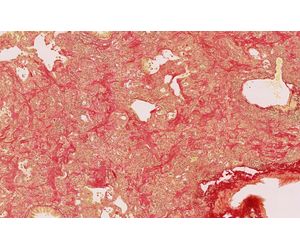

OracleBio’s team are experienced in the quantification of histological stains such as Picrosirius Red or Masson’s Trichrome to measure fibrotic changes in the lung. Within the whole tissue section, we provide accurate segmentation of the normal and lesioned parenchyma, avoiding the prominent vasculature and bronchial structures that can bias the data.

We can efficiently segment the fibrotic kidney into the distinct functional units (glomeruli) and then quantify collagen content within the kidney tissue using the quantification of Masson’s Trichrome or Picrosirius Red IHC staining. Quantifying collagen levels together with cellular content in models of kidney fibrosis is used to determine the effect of drug treatment in kidney fibrosis models.

Liver fibrosis is the excessive accumulation of extracellular matrix proteins including collagen that occurs in most types of chronic liver diseases including non-alcoholic steatohepatitis (NASH) and non-alcoholic fatty liver disease (NAFLD). We provide accurate quantification of advanced collagen and alpha smooth muscle actin (αSMA) deposition to reveal fibrotic changes in the liver. Our services provide highly detailed data which can be used to understand therapeutic response in liver tissue.